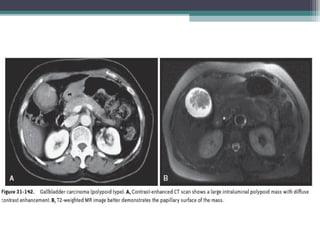

• IMAGING :

• CT :Typical finding include three patterns:

• 1)a mass replacing the gallbladder fossa (most common)

• 2)an intraluminal polypoid mass

• 3)gallbladder wall thickening.

• The mass fills most of the enlarged and deformed gallbladder, obscuring the

peripheral enhancement in the early phase and progressive enhancement in the

late phase.

• This type of gallbladder carcinoma often invades adjacent structures, including

the liver .

• An intraluminal polypoid mass is less common; differentiation ofpolypoid gb

carcinoma from benign polyps is based on size, with polypoid gallbladder

carcinoma typically larger than 1 cm .

• Most benign polyps, such as cholesterol polyps, and adenomas are small,

measuring less than 1 cm.

• Foramen ofWinslow lymph node and the superior pancreaticoduodenal node are the most frequent sites of nodal metastases • The other pathways of tumor spread c)Hematogenous metastasis to the liver, • d) intraductal tumor spread e) peritoneal seeding . • Biliary obstruction can be in present gallbladder carcinoma, because of direct invasion of the bile duct in the porta hepatis, to metastatic lymphadenopathy, or to intraductal spread of tumor . • IMAGING : • CT :Typical finding include three patterns: • 1)a mass replacing the gallbladder fossa (most common) • 2)an intraluminal polypoid mass • 3)gallbladder wall thickening. • The mass fills most of the enlarged and deformed gallbladder, obscuring the peripheral enhancement in the early phase and progressive enhancement in the late phase.

• 103.

• This typeof gallbladder carcinoma often invades adjacent structures, including the liver . • An intraluminal polypoid mass is less common; differentiation ofpolypoid gb carcinoma from benign polyps is based on size, with polypoid gallbladder carcinoma typically larger than 1 cm . • Most benign polyps, such as cholesterol polyps, and adenomas are small, measuring less than 1 cm. • The gallbladder wall thickening type of carcinoma may be difficult to distinguish from adenomyomatosis and cholecystitis (especially chronic cholecystitis and xanthogranulomatous cholecystitis) • MRI : • GB Ca usually have increased signal intensity and poorly delineated contours on T2- weighted images and either isointense or hypointense signal on T1-weighted images compared with the liver. • DWI : High b value DWI MRI helps in differenciating Benign from malignant lesions . Malignant lesions shows Higher signal than benign lesions at b value of 1000 s/mm2